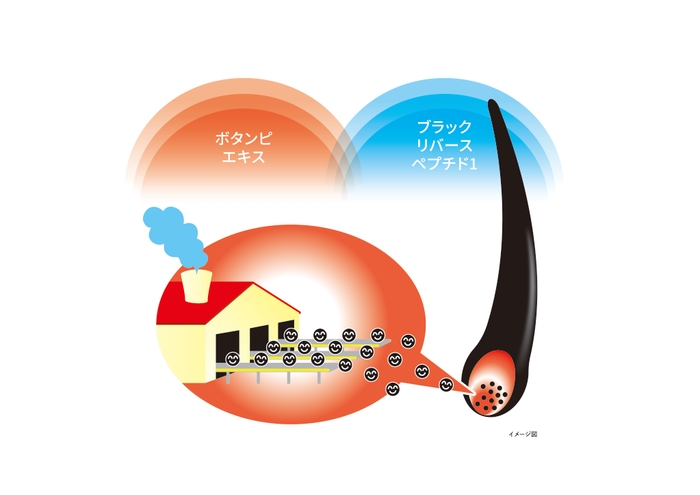

大正製薬株式会社(以下、当社)は、これまでボタンピエキス※1とブラックリバースペプチド1の組み合わせが、メラニンを作ることによって白髪改善効果を示すということを確認してきました。

当社はこのたび、Monasterium Laboratory(ドイツ・ミュンスター)※2、株式会社ネイチャーラボと共同で、新たにボタンピエキスとブラックリバースペプチド1の白髪改善効果を示すメカニズムを確認しました。

ここまで白髪になるメカニズムをご説明しましたが、次にボタンピエキスとブラックリバースペプチド1がどのように白髪を改善するのかご説明します。

ボタンピエキスは毛包のメラノサイトにおいて、メラニンをつくるメラノソームの構成タンパク質『Gp100』の量を増加させる傾向があることがわかりました。

さらにボタンピエキス及びブラックリバースペプチド1を組み合わせることで、毛包内のメラニンの量を増加させることがわかりました。

研究成果のまとめ

ボタンピエキス及びブラックリバースペプチド1の組み合わせは、メラノサイトでメラニンを作り出すメラノソームを形成・成熟化させ、メラニンの産生を促し白髪改善作用を発揮することが期待されています。